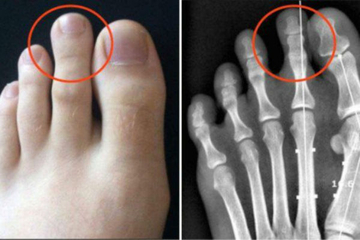

Lifestyle EVO ZAŠTO SAMO 14% STANOVNIŠTVA IMA DUŽI DRUGI PRST: Gledaćete ih drugim očima! 14.02.2022. | 13:56